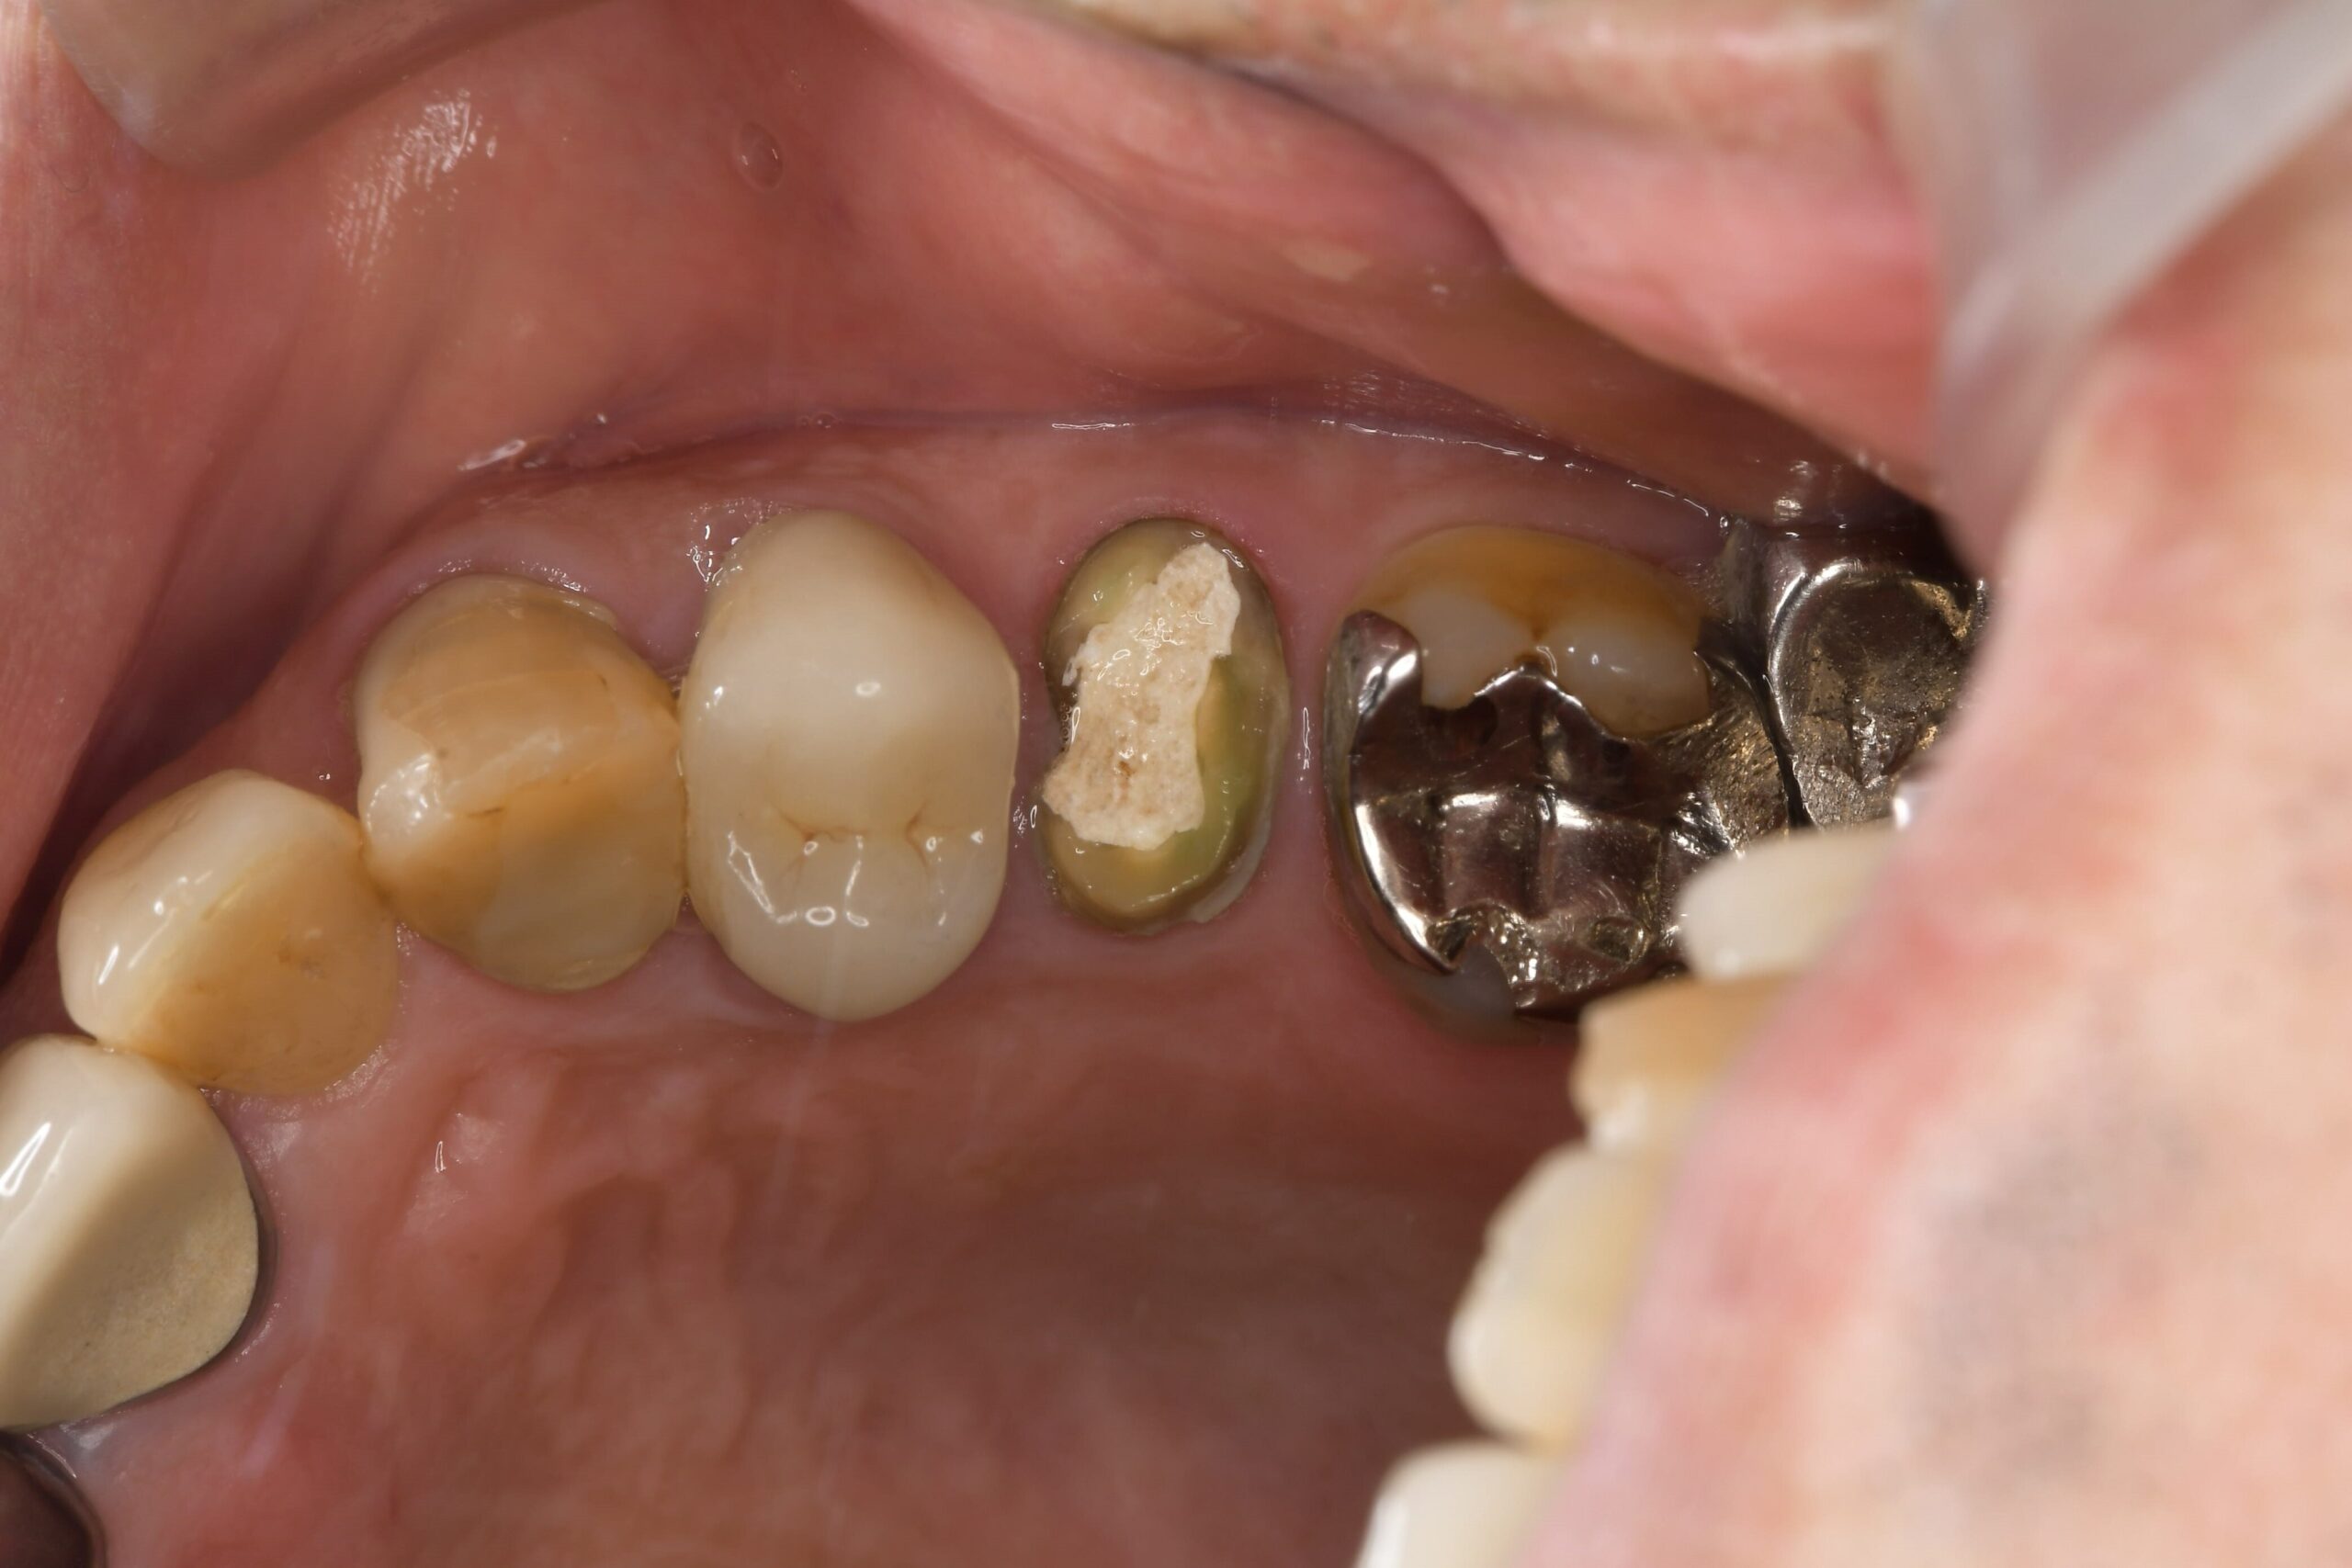

他院での根管治療歴がある左上5番ですが、マイクロスコープでの視診において、歯の根元に「破折(はせつ)」、つまりヒビが入っていることが確認されました。また、そのヒビが原因となり細菌感染が広がり、根っこの先に膿が溜まる「根尖病変(こんせんびょうへん)」も認められました。

念のため、歯内療法(根の治療)の専門医とも連携し診断を仰ぎましたが、「破折が明確であり、これ以上の保存(歯を残すこと)は難しい。抜歯が望ましい」という結論に至りました。